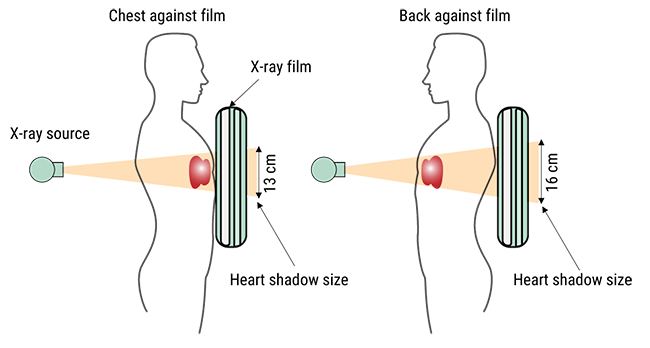

Chest x-ray is one of the most common imaging tests performed in clinical practice, typically for cough, chest pain, and shortness of breath, chest wall trauma, and assessment of occult disease. The two images show the difference between AP and PA images in representing the heart shadow size. Standard x-rays are performed with the patient standing facing the x-ray film or the digital cassette. The tube emits x-rays through the patient from back to front, reducing the magnification of the heart and other anterior structures that are situated close to the film in the PA position.

As a conclusion, a PA beam view of the chest allows more accurate representation of heart size as the heart is positioned closer to the detector and is therefore less magnified.

Heart is positioned closer to the detector and is therefore less magnified